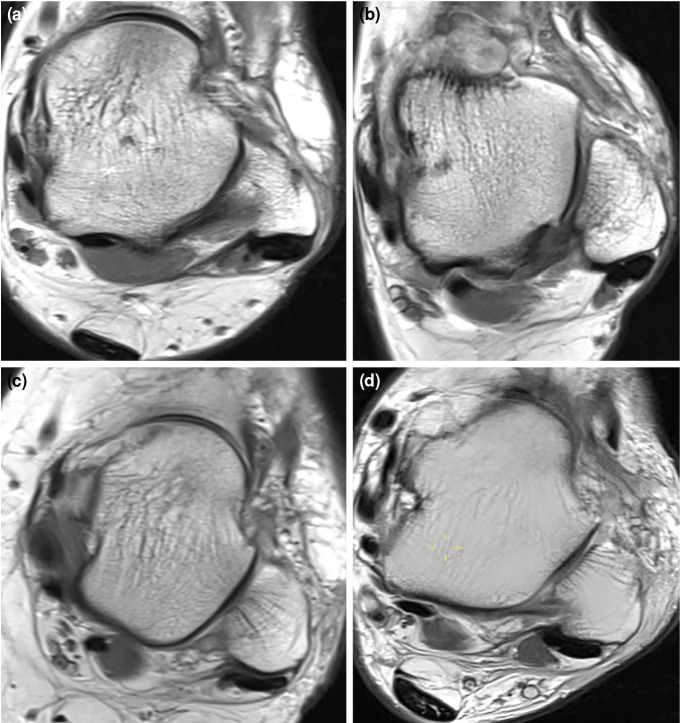

Patients and methods: Between January 2016 and December 2020, a total of 849 ankle MRIs (427 right foot, 422 left foot) in 738 patients (274 males, 464 females; mean age: 43.4±14.3 years; range, 15 to 70 years) were retrospectively analyzed. Among ankle pathologies, peroneal and flexor hallucis longus (FHL) tendinopathies were evaluated. Among the anatomical variations, retromalleolar fibular groove (RMFG) shape, os peroneum, os trigonum, peroneus quartus (PQ), flexor digitorum accessorius longus (FDAL), low-lying peroneus brevis (PB) and FHL muscles were examined. The distance of the PB and FHL musculotendinous junctions (MTJs) from designated reference points was measured. Cut-off values for PB and FHL musculotendinous junction distances were determined by receiver operating characteristic (ROC) analysis. For the reliability analysis of measurements performed by two researchers, intraclass correlation coefficient (ICC) values were calculated.

Results: Bilateral ankle MRIs of 111 patients were evaluated. The PB, PL, and FHL tenosynovitis were observed in 29.6%, 34.9%, and 38.8% of all ankles, respectively. The PB and PL tendon tears were found in 12.2% and 3.9%, respectively. A total of 47.1% of the RMFG shapes were concave, 36.7% were flat, 12.4% were convex, and 3.8% were irregular. The PQ, FDAL, os peroneum, and os trigonum were detected in 13.8%, 3.1%, 16.6%, and 20.5% of the ankles, respectively. The cut-off value of PB MTJ distance that would cause a PB tendon tear was 4.40 mm distal from reference point. The cut-off value of FHL MTJ distance that would cause FHL tendinopathy was 4.15 mm distal from reference point. The study had a statistically significantly high level of consistency between the experts (ICC=0.85).